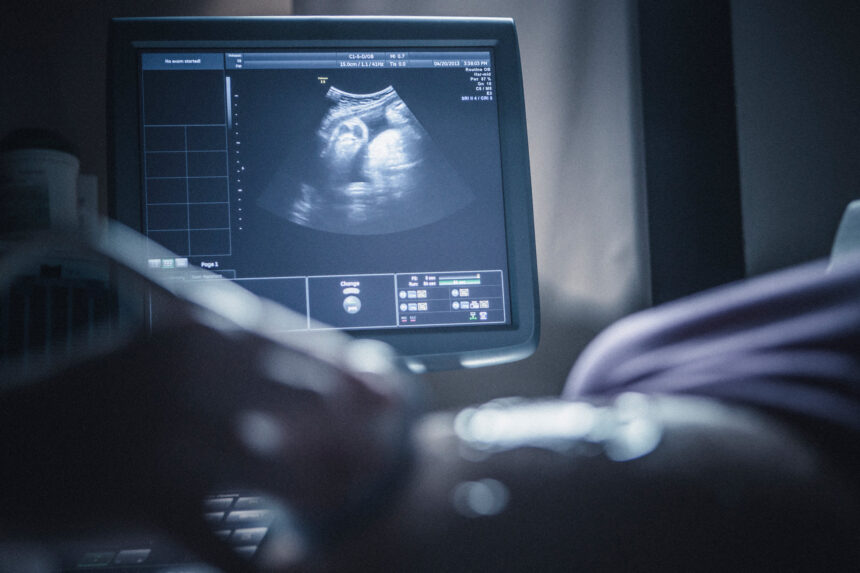

Ultrasounds are fundamental tools for understanding and tracking your pregnancy. This non-invasive imaging technique uses sound waves to provide detailed, real-time visuals of your developing baby. It provides a way to monitor progress and detect key details at various stages of pregnancy, including the first, second, and third trimesters. Here’s how pregnancy ultrasounds help with monitoring progress and promoting maternal and fetal health:

The first trimester marks the beginning of your pregnancy, and ultrasounds play a key role during this initial period. When you’re between six and twelve weeks pregnant, an initial ultrasound can help confirm your pregnancy by detecting the fetal heartbeat.

It is during this stage that healthcare providers estimate your due date based on the baby’s size. Doctors can also use the ultrasound to check for multiple fetuses at this appointment.

During the second trimester, your doctor can complete a detailed anatomy scan. This pregnancy ultrasound is typically done between 18 and 20 weeks.

It assesses your baby’s growth and anatomy, providing valuable information about their development, from the brain and heart to the fingers and toes. Parents-to-be can plan a gender reveal during this stage if they choose to learn their baby’s gender.